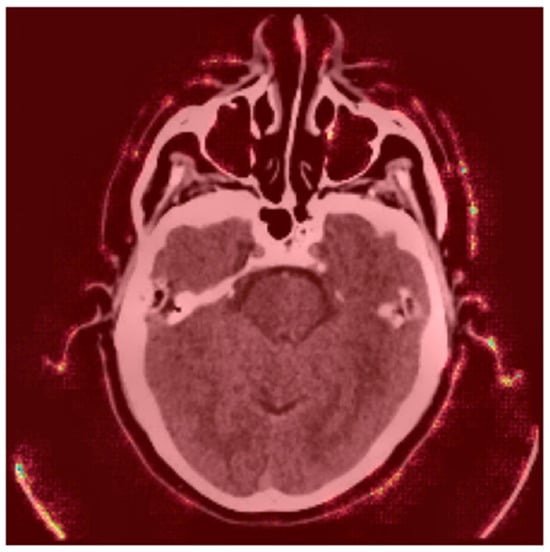

4.4. Stroke Prediction Visualization

- Red Regions (High Stroke Probability): These areas, highlighted in red, represent regions where the model detected features strongly associated with stroke, such as hyperdense hemorrhagic lesions or ischemic hypoperfusion. The red regions in the left hemisphere, for instance, correspond to the hyperdense clot, a key indicator of a hemorrhagic stroke.

- Green Regions (Low Stroke Probability): Green areas indicate regions with minimal influence on stroke prediction, typically healthy brain tissue or non-stroke-related anatomy.

- Yellow Outlines (LIME Segments): The image is divided into superpixels marked by yellow boundaries. LIME perturbs these segments to assess their impact on the model’s prediction. By masking and observing the changes in the prediction, LIME identifies the critical regions that drive the model’s decision-making process.